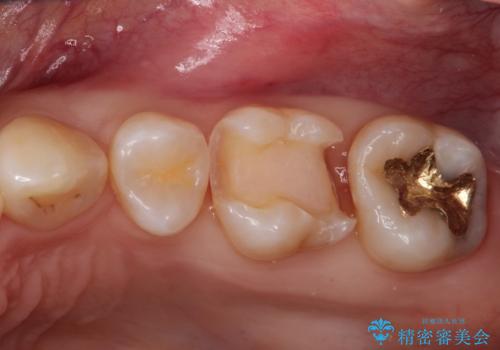

- 他院で虫歯になっていると指摘され来院されました。適合の良いゴールドインレーによる治療がされていましたが、違う部分が虫歯になってしまっていました。審美性の良いセラミックインレーを希望されました。

ゴールドインレーを除去し、その下で広がっていた虫歯をきれいに取り除きました。